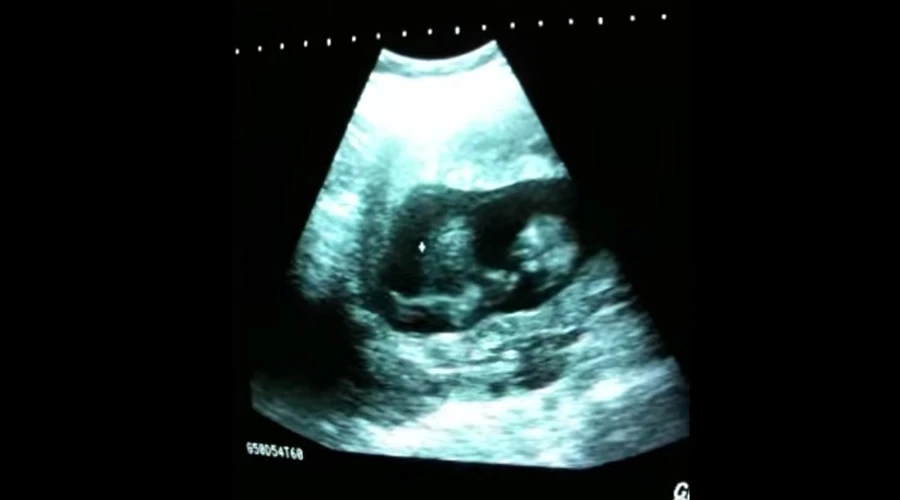

En el video, que corresponde a una ecografía de rutina, se puede observar a la bebé tomando repetidamente impulso a manera de columpio, dentro del útero de su madre.

Sherine Gayle-Slater, la madre de la bebé, recordó que este corresponde a una ecografía tomada “en algún momento entre las 8 y 12 semanas de embarazo, porque no podía sentir sus movimientos”.

“Si no era por la ecografía, no lo hubiera creído”, aseguró.